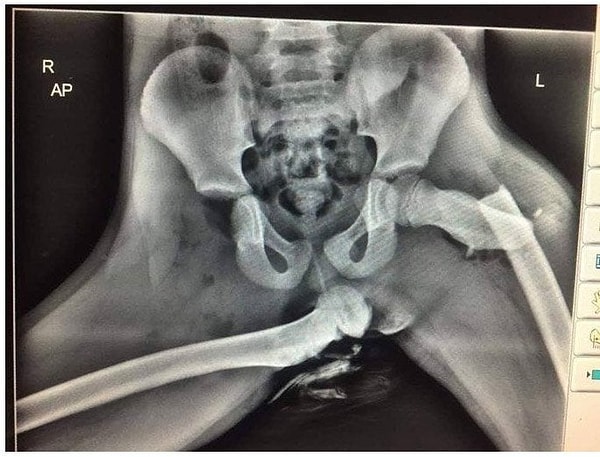

9. Почему не стоит класть ноги на переднюю панель: последствия аварии

Этот рентгеновский снимок наглядно демонстрирует, почему всем пассажирам в автомобиле нужно держать ноги на полу.